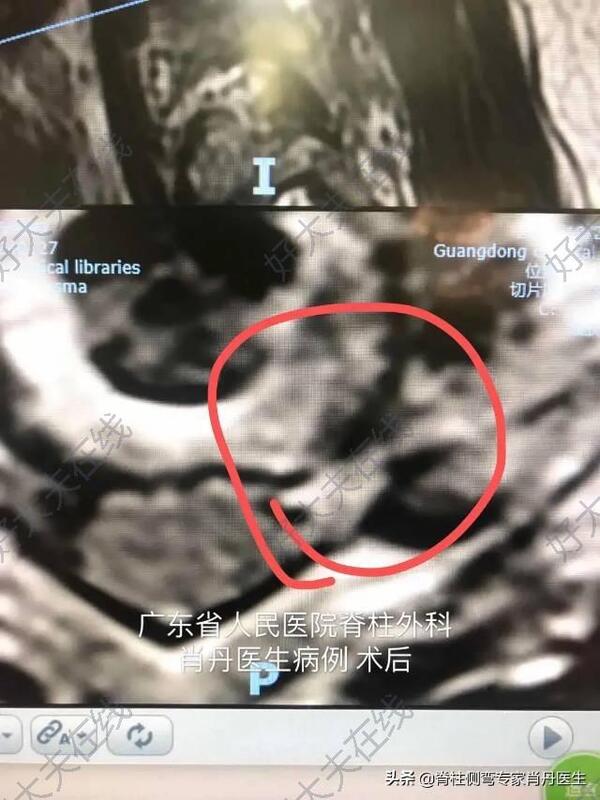

术后第二天查房,患者说术前的疼痛完全缓解!高兴得竖起来大拇指!